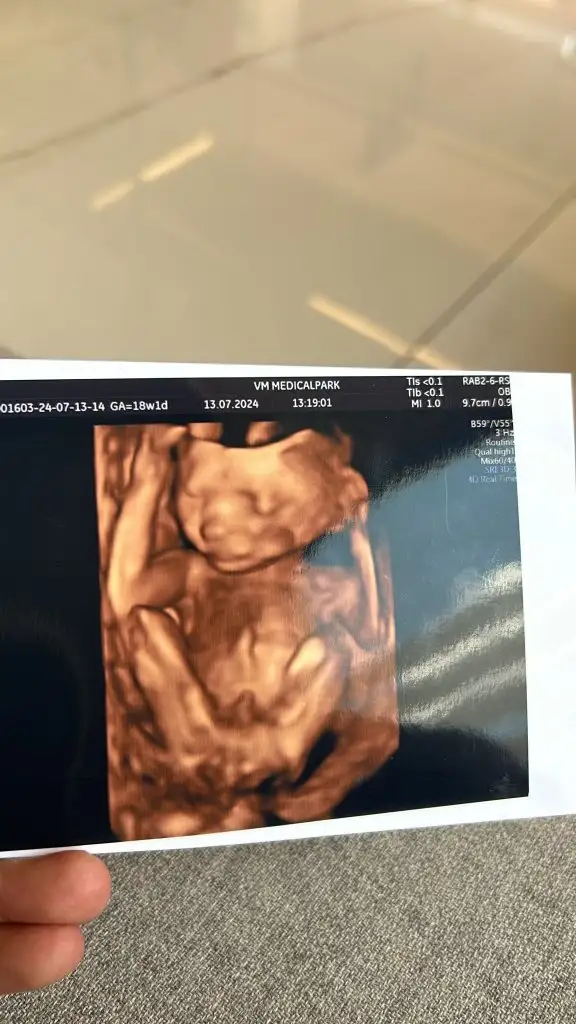

Bebiş ektedir efenim